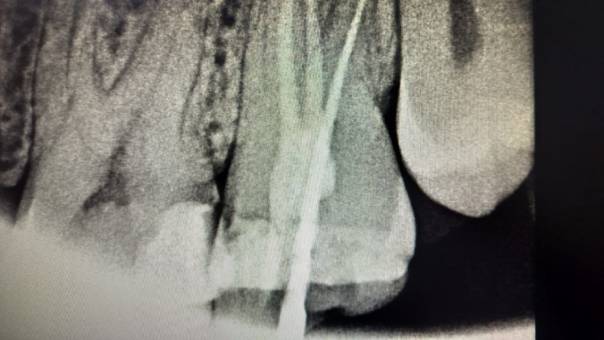

Clinical and Radiographic Findings:

On examination, mild tenderness was noted when

tapping on tooth 27. A radiographic evaluation

revealed that the distal canal of the tooth had been

inadequately treated and left unfilled. This had led

to a localized periapical infection.

Locating the distal canal

After Obturation

Unfilled distal canal pre-operation